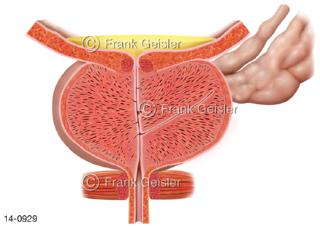

Bildergalerie Urogenitalsystem

Bilder zum Urogenitalsystem mit Urogenitalorgane, Urogenitaltrakt, zum Harn- und Geschlechtsapparat, Harnorgane und Geschlechtsorgane, Organe der Harnwege und der Fortpflanzung, Harnorgane und Geschlechtsorgane im männlichen und weiblichen Urogenitalsystem